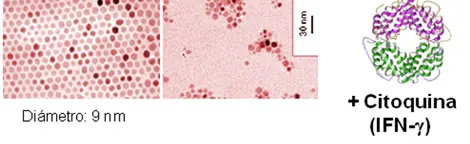

P. M. Primero sintetizamos las nanopartículas de óxido de hierro y las recubrimos de un componente que las haga estables y solubles en agua, como por ejemplo DMSA (ácido dimercaptosucínico) Después las unimos a un fármaco antitumoral, una citoquina, que es una proteína que activa el sistema inmune, siempre y cuando exista una concentración elevada de ella. Posteriormente, se introduce en sangre una disolución acuosa de estas nanopartículas portadoras del fármaco y mediante un imán, se concentran en la zona del tumor, como se puede ver en el esquema que se muestra más abajo.